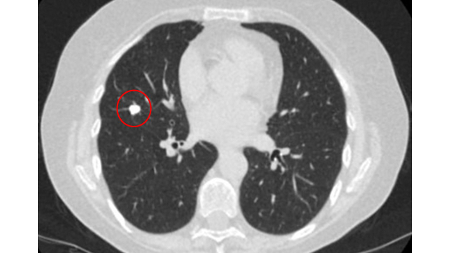

Computed tomography (CT) showing a benign calcified granuloma in the right middle lobe, stable >10 years. The patient reported previous pneumonia on the same side

From the collection of Dr George Tsaknis, MD, PhD, FRCP(London), MRQA, MAcadMEd, PGCert; used with permission